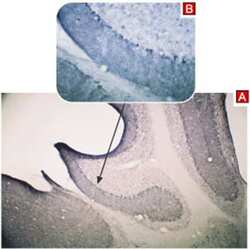

PA5-77307 IHC

Full details

Method:

Other validation